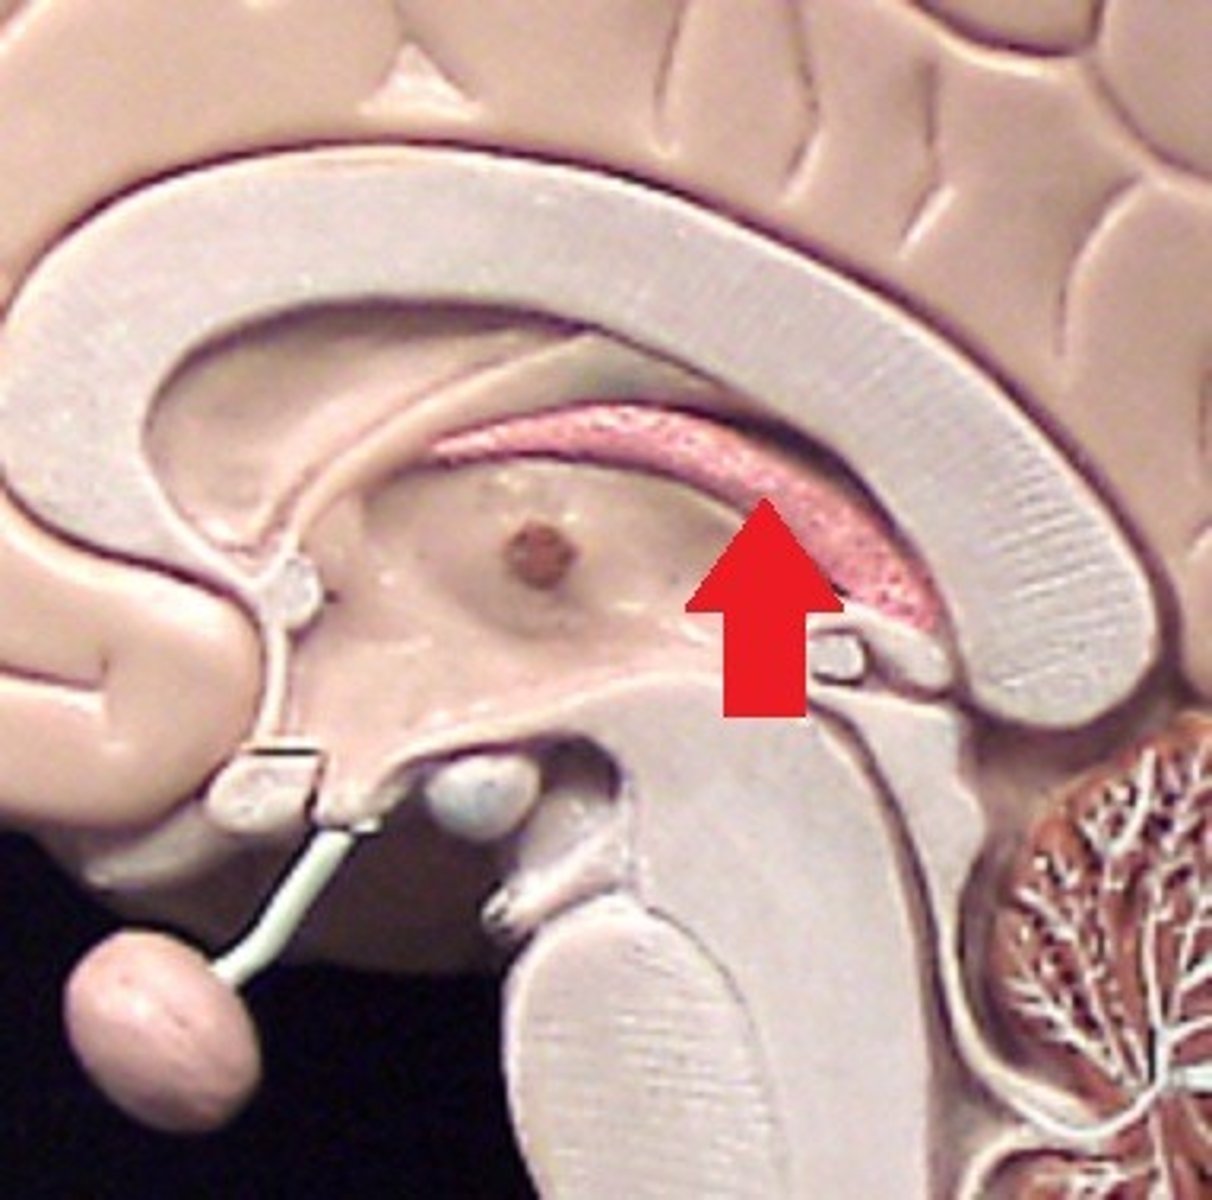

Lateral Ventricle

Third Ventricle

Cerebral Aqueduct

Forth Ventricle

Corpus Callosum

Fornix

Thalamus

Pineal Gland

Superior Colliculi

Inferior Colliculi

Midbrain

Hypothalamus

MIdsagittal View of brain